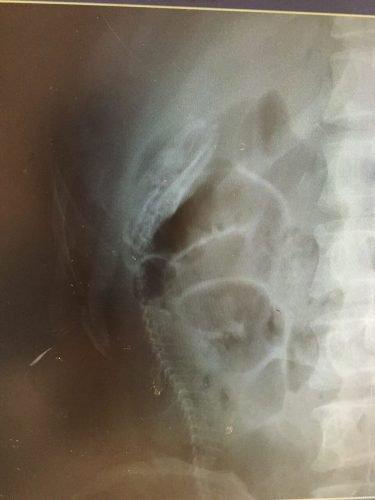

9-Uma faca

Como essa pessoa conseguiu inserir uma faca dentro de seu corpo através do seu ânus nós não sabemos. Mas, inicialmente, ela parece ter sido colocada primeiramente pelo cabo. Isso deve ter sido realmente doloroso e gerado enormes consequências. Infelizmente não sabemos o destino que se deu para essa pessoa.